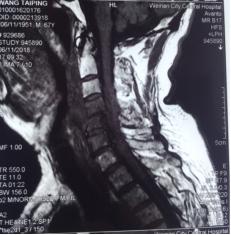

来市中心医院后,患者四肢肌力上肢1-2级,下肢1级。双下肢腱反射未引出。自胸骨柄以远躯干部位感觉减退。入院后给以各项常规检查,血常规显示白细胞计数12.54×109/L,中性粒细胞绝对值10.85×109/L,,中性粒细胞百分比86.5%,血沉22mm/h,超敏C反应蛋白69.4mg/L。空腹血糖13.88mmol/L。颈椎核磁检查显示颈4/5椎间隙狭小,颈4.5.6椎体T1像低密度,椎体前缘出现炎性浓集。入院初步诊断:颈椎体感染,合并椎间隙脓肿形成,四肢不软瘫,糖尿病II型。在治疗早期即给以广谱抗生素头孢哌酮舒巴坦钠静滴.3.0g,q8h;并口服莫西沙星片,0.4g,qd,使用阿卡波糖控制血糖。再次完善相关检查。全身放射性同位素骨扫描未见肿瘤表象。结核TB淋巴细胞斑点试验阴性,布氏杆菌滴度测定阴性。经治疗,患者体温平稳,血沉,超敏C反应蛋白水平下降明显。后期再次复查颈椎核磁,发现颈椎椎体4.5前缘形成更大的积液表现,椎管内也有形成。随后在B超定位下行颈前肿物穿刺抽吸术,抽出含血浑浊液2ml,分泌物抗酸染色阴性,常规染色图片发现多量的阳性球菌,细菌培养3未见细菌生长。